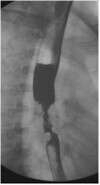

据61岁的王先生自诉,他进行性吞咽困难已经长达3个月时间 ,通过市中心医院确诊为食道癌。放射科主任余开湖博士为王先生采用碘125粒子支架治疗食管癌,使食管通畅,并在腔内用碘125粒子放射治疗食管癌。目前患者康复出院。

据余主任介绍,所谓碘125粒子支架治疗方法,就是用支架撑开接近堵塞的食道,让患者能正常进食,确保患者身体营养需要的同时,采用放射性碘125粒子植入术,其方法是通过影像学导引技术(超声、CT、MRI)将放射性核素直接植入肿瘤靶体积内或肿瘤周围(腔内),通过放射性核素持续释放射线对肿瘤进行杀伤,达到治疗肿瘤的目的。由于放射性粒子只对局部持续作用,因此对肝肾及全身脏器功能影响较少,不良反应较轻。近距离腔内照射主要应用于食道癌、胆管癌。